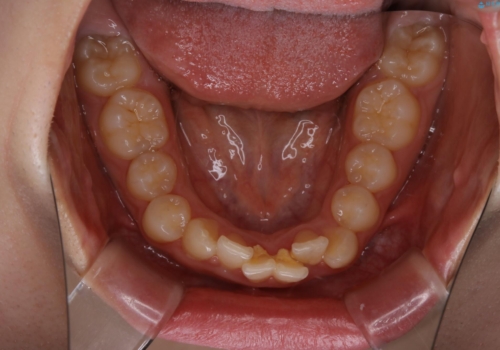

前歯のがたつきとディープバイト:インビザライン治療

- 前歯のがたつきと、噛み合わせが深いことを気にされてご相談にいらした方です。

インビザラインにて治療を行いました。

一般的に、歯冠(歯の長さ)が短い方はインビザライン治療に時間がかかりやすい傾向にあります。

歯の移動量に対して大きなブラックトライアングルもできることなく綺麗に並べることができ、大変喜んでいただけました。